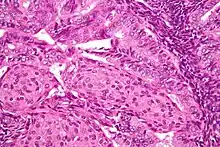

.jpg.webp)

In endometrioid adenocarcinoma, the cancer cells grow in patterns reminiscent of normal endometrium, with many new glands formed from columnar epithelium with some abnormal nuclei. Low-grade endometrioid adenocarcinomas have well differentiated cells, have not invaded the myometrium, and are seen alongside endometrial hyperplasia. The tumor's glands form very close together, without the stromal tissue that normally separates them. Higher-grade endometrioid adenocarcinomas have less well-differentiated cells, have more solid sheets of tumor cells no longer organized into glands, and are associated with an atrophied endometrium. There are several subtypes of endometrioid adenocarcinoma with similar prognoses, including villoglandular, secretory, and ciliated cell variants. There is also a subtype characterized by squamous differentiation. Some endometrioid adenocarcinomas have foci of mucinous carcinoma.[47]

The genetic mutations most commonly associated with endometrioid adenocarcinoma are in the genes PTEN, a tumor suppressor; PIK3CA, a kinase; KRAS, a GTPase that functions in signal transduction; and CTNNB1, involved in adhesion and cell signaling. The CTNNB1 (beta-catenin) gene is most commonly mutated in the squamous subtype of endometrioid adenocarcinoma.[48]